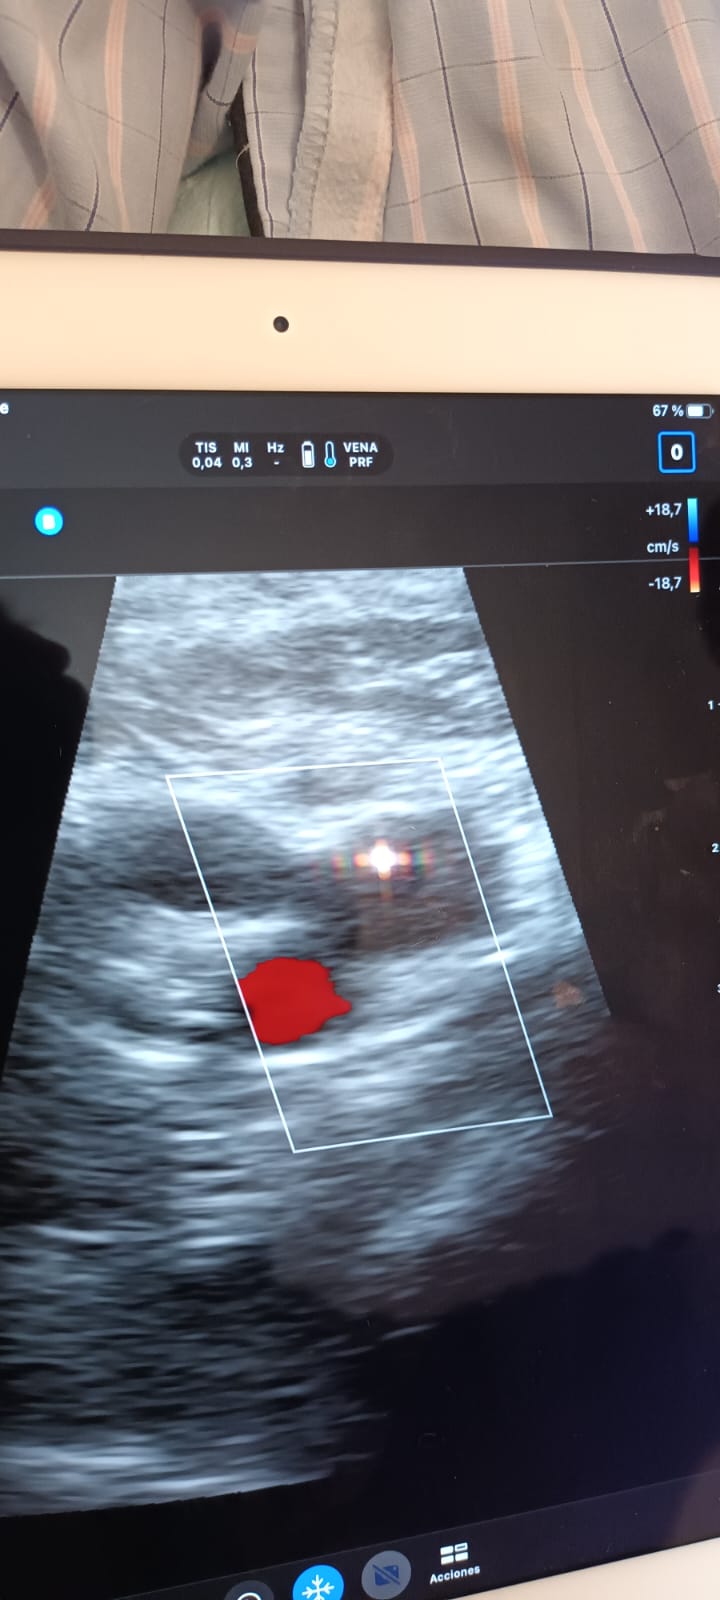

Al realizar ecografía Doppler miembro inferior derecho, objetivamos en región ilíaca, femoral, y poplítea, ocupación por material ecogénico, y que no resultan compresibles.

Realizamos también ecocardioscopia, encontrando un trombo en transición en ventrículo derecho.